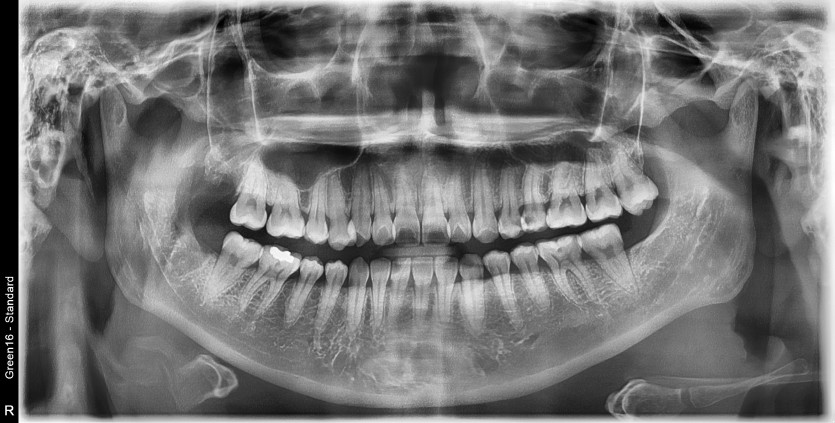

#18,48 사랑니 발치

구강 외과 전문의가 당일 발치했습니다.